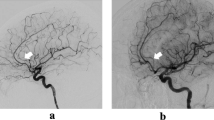

The brain parts vascularized by the SCA are listed in Table 2. The most frequently vascularized parts were the paraterminal and parolfactory gyri, the rostrum, and genu of the corpus callosum, the lamina terminalis, and the anterior commissure. In five cases, we found a perforating SCA branch that vascularized the fornix (Figs. 7, 8).

In some specimens, we observed perforating branches of the SCA artery supplying the fornix (Fig. 7). In 5 of the 19 specimens, the SCA supplied the anterior fornix; these arteries were significantly broader and longer than those not supplying the fornix. Moreover, 5 of the 6 SCA with a diameter greater than 0.7 mm supplied the fornix.

Similarly, the SCAs supplying the anterior commissure, the body of the corpus callosum, and the anterior cingulate gyrus were larger and longer than those that did not (Table 3). Since the fornix and cingulate gyrus belong to the Papez circuit [15], we hypothesize that memory disorders might be due to ischemia of the SCA.